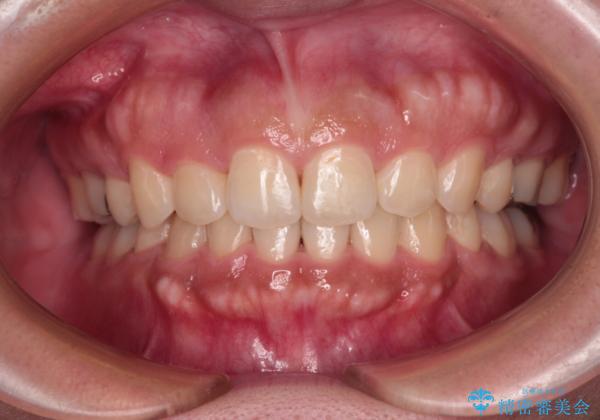

急速拡大とワイヤー抜歯矯正で唇を閉じやすく

- 口元の突出感を気にして来院された患者様です。

デコボコと口元の突出感が認められたため、上下左右の第1小臼歯4本を抜歯してのワイヤー矯正を行うこととしました。

上顎歯列の横幅が狭く、下顎大臼歯の歯軸が舌側に倒れていたため、急速拡大装置により上顎骨を側方に拡大し、咬み合わせを改善することとしました。

上顎歯列幅を拡大したことで、デコボコを容易に解消することができるようになったため、抜歯により得られたスペースを口元の突出感改善に利用することができました。